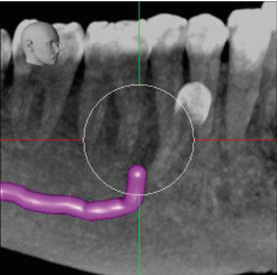

From a surgical perspective, the root of the supernumerary tooth is straight and its apex contacts the ID canal at the point at which the mental canal is given off (images 5 and 6). The only potential risk would be with downward pressure. In a surgical context there is a potential risk with any applied downward pressure.

5. Oblique mesio-distal cross-section through the supernumerary tooth, showing the neurovascular canal in contact with its root apex (mental foramen arrowed).